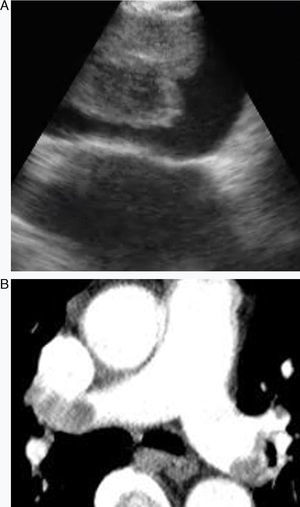

El tromboembolismo pulmonar (TEP) es un trastorno clínico relacionado con una oclusión súbita de la arteria pulmonar. Tiene una alta tasa de mortalidad y morbilidad. El TEP puede diagnosticarse erróneamente en los pacientes con comorbilidades. El empleo sistemático de angio-TC de tórax multicorte es la técnica de primera elección para el diagnóstico del TEP. El empleo de soluciones de contraste y la irradiación son sus principales limitaciones en los casos de insuficiencia renal y en el embarazo1,2. Por consiguiente, en estas distintas situaciones son esenciales otras pruebas diagnósticas (figs. 1 y 2).

La EBUS se emplea generalmente para la biopsia de las adenopatías mediastínicas e hiliares o las masas. Las arterias pulmonares son del orden de 5mm en la zona traqueobronquial. Por consiguiente, la EBUS puede visualizarlas con facilidad. Nosotros utilizamos una sonda de ecografía convexa (Olympus EBUS-CV-180, Tokio, Japón) para la evaluación broncoscópica. El diámetro externo de la CP-EBUS es de 6,9mm. Dispone de un canal de trabajo de 2,0mm y de una óptica de visión anterógrada oblicua de 30grados. La penetración máxima del transductor ecográfico lineal es de 50mm, y está conectado a un procesador que permite visualizar el flujo de los vasos mediastínicos e hiliares10.Casoni et al. utilizaron la EBUS en un paciente que presentaba una lesión intraarterial de baja densidad sospechosa en la angiografía pulmonar y publicaron por primera vez el diagnóstico de un TEP4. Aumiller et al. diagnosticaron de forma incidental un TEP en el examen de determinación del estadio de 3 pacientes con cáncer de pulmón mediante EBUS. Posteriormente se inició un estudio multicéntrico para evaluar la presencia de TEP mediante CP-EBUS en las primeras 24h siguientes al diagnóstico del TEP mediante angio-TC. Se detectaron con facilidad los trombos en las arterias pulmonares en 28 de 32 pacientes. Un total de 97 de los 101 trombos diagnosticados mediante angio-TC fueron confirmados con la EBUS (sensibilidad del 96%). La EBUS permite visualizar el tronco pulmonar, las arterias pulmonares principales y las arterias lobulares. Uno de los 4 trombos que no pudieron visualizarse se encontraba en la arteria del lóbulo medio y 3 estaban en la arteria del lóbulo superior izquierdo. Durante el estudio, ninguno de los pacientes presentó complicación alguna. En consecuencia, los autores llegaron a la conclusión de que la EBUS era una prueba diagnóstica fiable para el TEP de localización central5. Después de este estudio, se han publicado múltiples descripciones de casos de uso de la EBUS en el diagnóstico del TEP6,11-13.

En el presente estudio, todos los pacientes estaban hemodinámicamente estables y fueron sedados durante la broncoscopia. La EBUS se llevó a cabo utilizando un abordaje oral, con anestesia consciente en todos los pacientes. Se mantuvo un registro constante de la presión arterial, la frecuencia del pulso y la saturación de oxígeno durante todos los procesos. Las arterias pulmonares principales se visualizaron tras la evaluación de las adenopatías mediastínicas en todos los casos. El broncoscopista sabía dónde estaban los defectos de repleción observados en las arterias pulmonares en la TC. Las arterias pulmonares permeables no muestran ecos. En nuestros casos, cuando se visualizaron zonas ecogénicas, el broncoscopista confirmó la presencia del trombo con el empleo del modo Doppler.